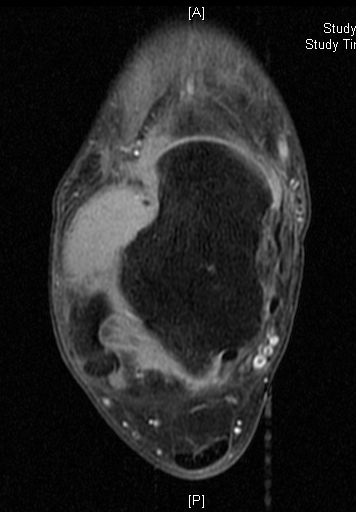

Shows multiloculated, heterogeneous mass.

“Triple Signal Intensity sign”; hypointense, isointense and hyperintense with fat on T2 – weighted MRI imaging. This sign is present in 30 to 50% of the cases. (Fig.3)

Under contrast enhancement Synovial Sarcoma appears heterogeneous and demonstrate areas of nodular enhancement.

In approximately 30% of cases a multiple vascular cannel may be identified

Synovial sarcomas may have a cystic appearance and are often mistaken for ganglion cysts especially those adjacent to tendons and in the foot and ankle.